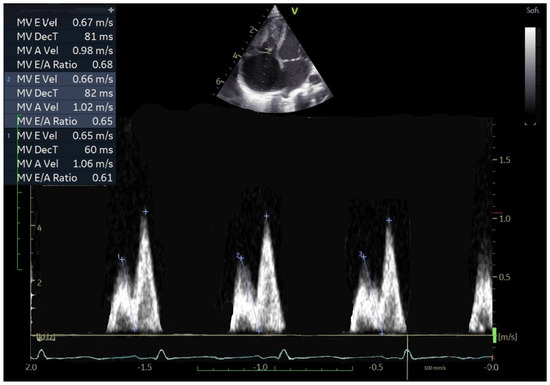

Echocardiographic Markers of Right Ventricle Diastolic Dysfunction in Neonates and Infants with Congenital Heart Disease

Background: Assessing right ventricular (RV) diastolic function by echocardiography in pediatric patients remains complex, particularly in congenital heart disease (CHD) characterized by RV pressure overload. The geometric peculiarities of the RV, respiratory influences, and age-dependent maturational changes complicate interpretation of Doppler-derived indices. This study aimed to characterize tricuspid valve (TV) pulsed-wave Doppler E/A inflow patterns in infants with CHD and RV pressure overload, evaluated shortly after surgical or percutaneous intervention. Methods: Echocardiographic analysis included TV E- and A-wave velocities obtained by pulsed-wave Doppler and measurement of E-wave deceleration time (EDT). Beat-to-beat variability was quantified over three consecutive cardiac cycles. Data were compared with a large cohort of age-matched healthy children. Results: Fifty-seven infants with CHD (35 pulmonary stenosis; 22 tetralogy of Fallot), examined 12–48 h post-intervention, were compared with 134 healthy controls. CHD patients showed markedly reduced beat-to-beat variability of both E- and A-wave velocities (p < 0.001 and p = 0.007, respectively). A three-beat E/A inversion pattern—common in neonates but variable in healthy infants—was consistently observed in CHD patients (p < 0.001). A-wave velocities were significantly higher (p < 0.001), whereas E/A ratios (p < 0.001) and EDT values (p = 0.010) were significantly lower compared with controls. Conclusions: Infants with CHD and RV pressure overload exhibit a characteristic Doppler pattern consisting of E/A ratio inversion, reduced beat-to-beat variability, increased A-wave velocity, and shortened E/A ratio and EDT. These findings may serve as practical and reproducible indicators of RV diastolic dysfunction in the early post-intervention period in neonates and infants. Full article